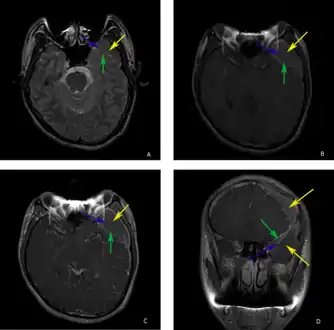

-

a-d)individual with complicated arachnoid cyst -

The diagnostic process typically begins with a medical history workup followed by a medical examination by a physician. Imaging tests, such as CT scans and MRIs, help provide a clearer picture. The physician typically looks for fluid (or other bodily substance) filled sacs to appear in the scans, as is shown in the CT scan of a colloid cyst. A primary health care provider will refer an individual to a neurologist or neurosurgeon for further examination. Other diagnostic methods include radiological examinations and macroscopic examinations. After a diagnosis has been made, immunohistochemistry may be used to differentiate between epithelial cysts and arachnoid cysts.[2] These examinations are useful to get a general idea of possible treatment options, but can be unsatisfactory to diagnose CNS cysts.[3][5] Professionals still do not fully understand how cysts form; however, analyzing the walls of different cyst types, using electron microscopes and light microscopes, has proven to be the best diagnostic tool. This has led to more accurate cyst classification and correct course of action for treatments that are cyst specific. In the past, before imaging scans or tests were available, medical professionals could only diagnose cysts via exploratory surgery.[2]